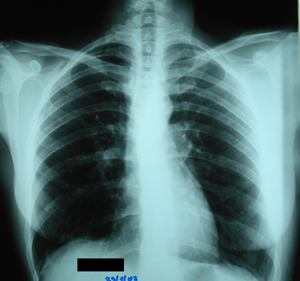

Εικόνα 3

Οπισθιοπροσθία ακτινογραφία θώρακος μετά από δεξιά θωρακοτομή και τμηματεκτομή του μέσου λοβού, δώδεκα χρόνια μετά από την επέμβαση.

Δεν διακρίνονται σημεία υποτροπής, ενώ φαίνονται τα clips του συρραπτικού εργαλείου που είχαν χρησιμοποιηθεί.